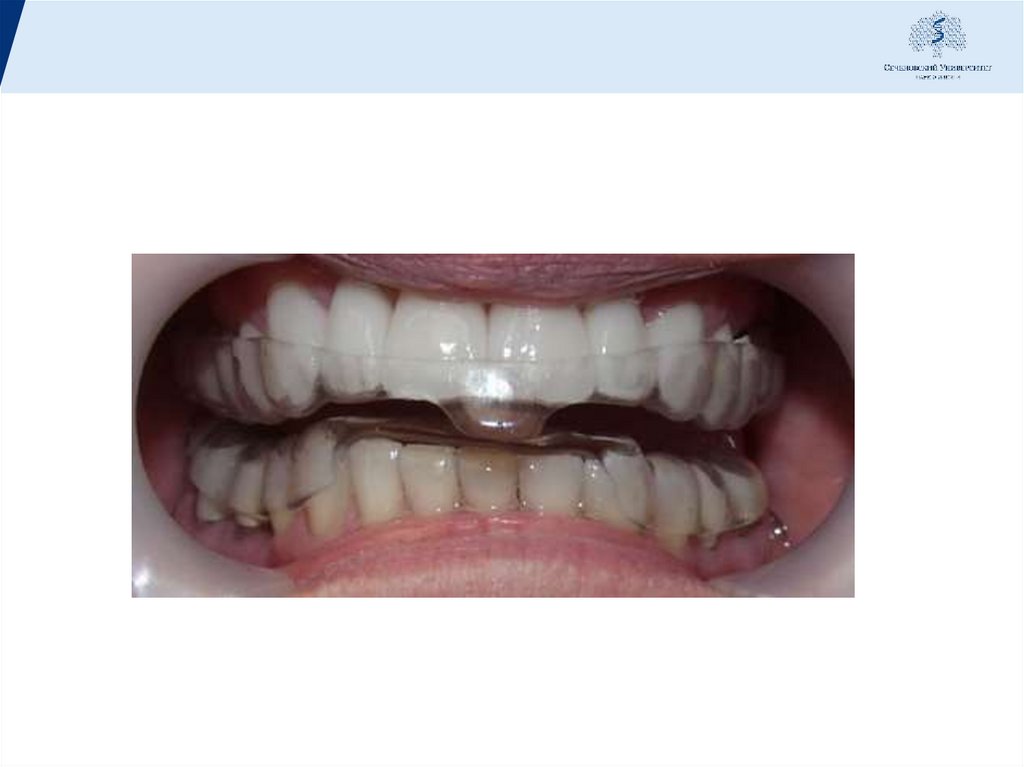

40. В шину включают все зубы, обеспечивая иммобилизацию по дуге.

Временные шины

изготавливают из

пластмассы. Различают

• капповые шины

• оральные

• вестибуло-оральные

многозвеньевые

Капповые шины охватывают окклюзионную часть

коронок зубов, их применение связано с завышением

окклюзионной высоты.

Пластмассовые шины - каппы, армированные

металлической или неметаллической арматурой и

временно фиксированные, обеспечивают наилучший

шинирующий эффект, одновременно позволяют

восстановить дефекты зубного ряда и улучшить

внешний вид пациента.

Вестибуло-оральные шины (круговые) покрывают

только часть вестибулярной поверхности зуба, не

мешают смыканию антагонистов и не оттесняют

десневой край.